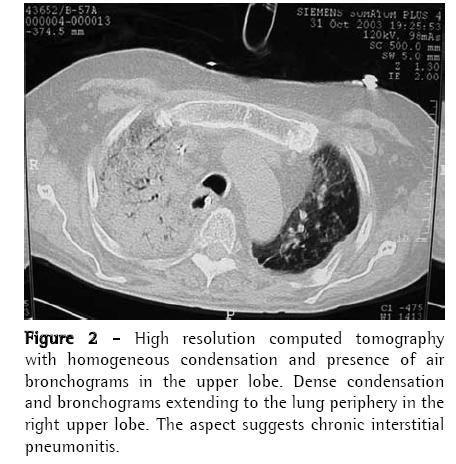

Case ReportA 56-year-old man diagnosed with IPF (using clinical, functional, tomographic and pathological criteria) five years prior, progressively evolved to dyspnea upon exertion and intense difficult-tocontrol cough with sparse mucoid expectoration. In the month preceding the lung transplantation, he presented hypoxemia and hypercapnia (arterial blood gas analysis with a PaO2 of 57 mmHg and arterial carbon dioxide tension of 45 mmHg at rest on room air at sea level), diffusing capacity of the lung for carbon monoxide at 29% of the predicted value, forced vital capacity of 40.8% (1.41 L), and forced expiratory volume in one second of 52.6% (1.31 L). Pulmonary perfusion scintigraphy revealed arterial flow of 76.7% for the right lung and 23.3% for the left lung. The laboratory tests for collagen-related diseases and the epidemiological investigation of known interstitial diseases were negative. During the five years of outpatient monitoring, the patient had been treated with corticosteroids (prednisone, 0.25 to 1 mg/kg/day), immunosuppressive agents (azathioprine or cyclophosphamide, 0.5 to 2 mg/kg/day), and an antifibrotic/immunomodulatory agent (interferon-γ1b) for four months. The transplantation was unilateral at left, corresponding to the minimal arterial perfusion and the greater intensity of the interstitial involvement according to the high-resolution computed tomography (HRCT) scan. Immediately after surgery, the patient evolved to thoracic instability due to the fracture of three ribs as a result of the osteopenic rib traction during the closure of the incision. He also presented ischemia of severe pulmonary reperfusion (arterial blood gas analysis with a PaO2/fraction of inspired oxygen ratio = 124). The patient was tracheostomized and remained on invasive mechanic ventilation (MV) for ten days, progressively recovering from hypoxemia. The immunosuppressive regimen began with 5 mg/kg of cyclosporine (12/12 h), 0.5 mg/kg/day of prednisone, and 2 mg/kg/day of azathioprine. In addition, anti-basiliximab interleukin-2 antibody was administered on postoperative days 1 and 4. Anti-methylprednisolone antibody (1 g) was also administered postoperatively. The patient was discharged from the intensive care unit to the semi-intensive care unit. However, on the eighth day in the semi-intensive care unit, he presented exacerbation of dyspnea, accompanied by the return of the dry cough and progressive crackling rales throughout the right hemithorax, and was therefore re-admitted to the intensive care unit. The patient was again submitted to an HRCT scan. In addition, fiberoptic bronchoscopy with bronchoalveolar lavage (BAL) was performed, together with transbronchial biopsy of the left lower lobe and the right upper lobe. All cultures tested negative, the BAL fluid presented a neutrophilic pattern, without eosinophils or hemosiderin-laden macrophages, and the histopathological analysis was inconclusive. A pulmonary arteriogram was performed, followed by thoracoscopic lung biopsy in three different regions of the right upper lobe to ensure that the disease was representative (Figures 1 and 2). The pulmonary arteriogram did not demonstrate thromboembolic disease. The biopsy culture was negative for bacteria, fungi, and mycobacteria. Herpes simplex virus and cytomegalovirus tests were also negative. Direct immunofluorescence for Chlamydia pneumoniae, Legionella pneumophila, and Mycoplasma pneumoniae, as well as for antigenuria for L. pneumophila serotype 1, were negative. The histological study of the biopsy of the three right lung areas showed an exclusive pattern of UIP, similar to the left native lung (Figure 3). Pulse therapy with 1 g of methylprednisolone was performed for three consecutive days. The patient remained on invasive MV, then evolved to sepsis caused by infection with Klebsiella pneumophila and Pseudomonas aeruginosa. On day 141 of the hospital stay, after the patient had been on invasive MV and using noradrenaline (0.2 µg/kg/day) for 109 days, transplant of the right native lung was carried out - bilateral sequential transplantation with more than a month interval - regardless of the relative contraindications: high dose of corticosteroid (>20 mg/day), MV, and sepsis treatment. (6)

The radiological imaging demonstrated condensation in the middle, upper, and lower right lobes, and the established diagnosis was IPF exacerbation in the native lung, mainly characterized by the UIP histological aspect (nonuniform and multifocal infiltrate, with inflammatory and fibrous thickening of the alveolar interstitium, pulmonary cysts, peribronchiolar fibrosis, alveolar hyperplasia, and absence of hyaline membranes), and the absence of microbial increase in lung tissues and cardiovascular decompensation. It is known that, in IPF, the lung becomes progressively collapsed, which can simulate images of pulmonary condensation. The accelerated variant of IPF has recently been described and should have its diagnosis characterized by ruling out other causes of exacerbation. The literature mentions, in unilateral lung transplantation, chronic progression of IPF in the native lung. However, there have been no reports of acute progression. This is the first case described in the national literature as IPF in its accelerated phase.